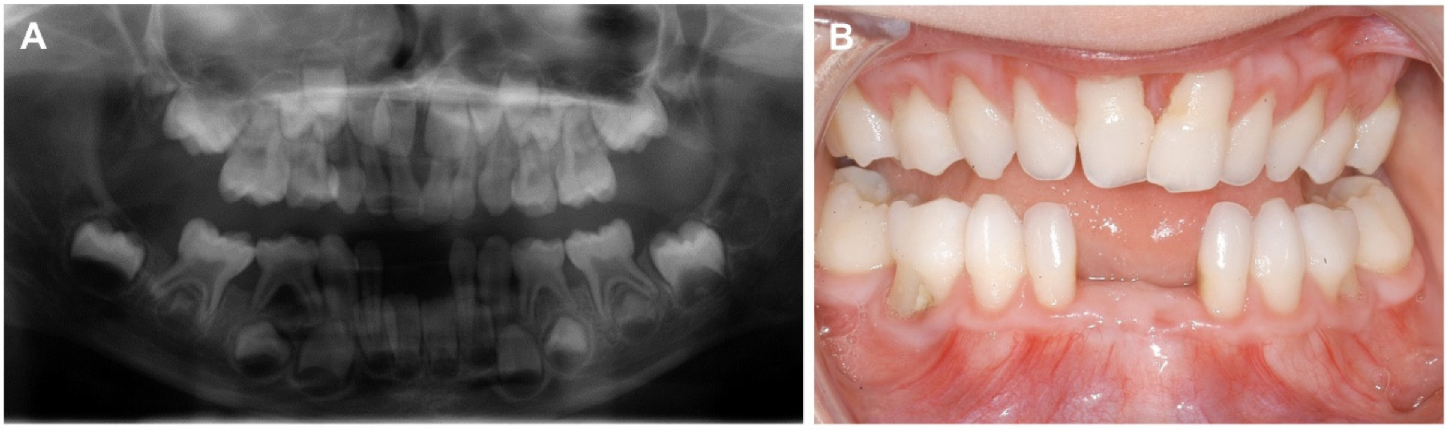

2.3. Oral Examination